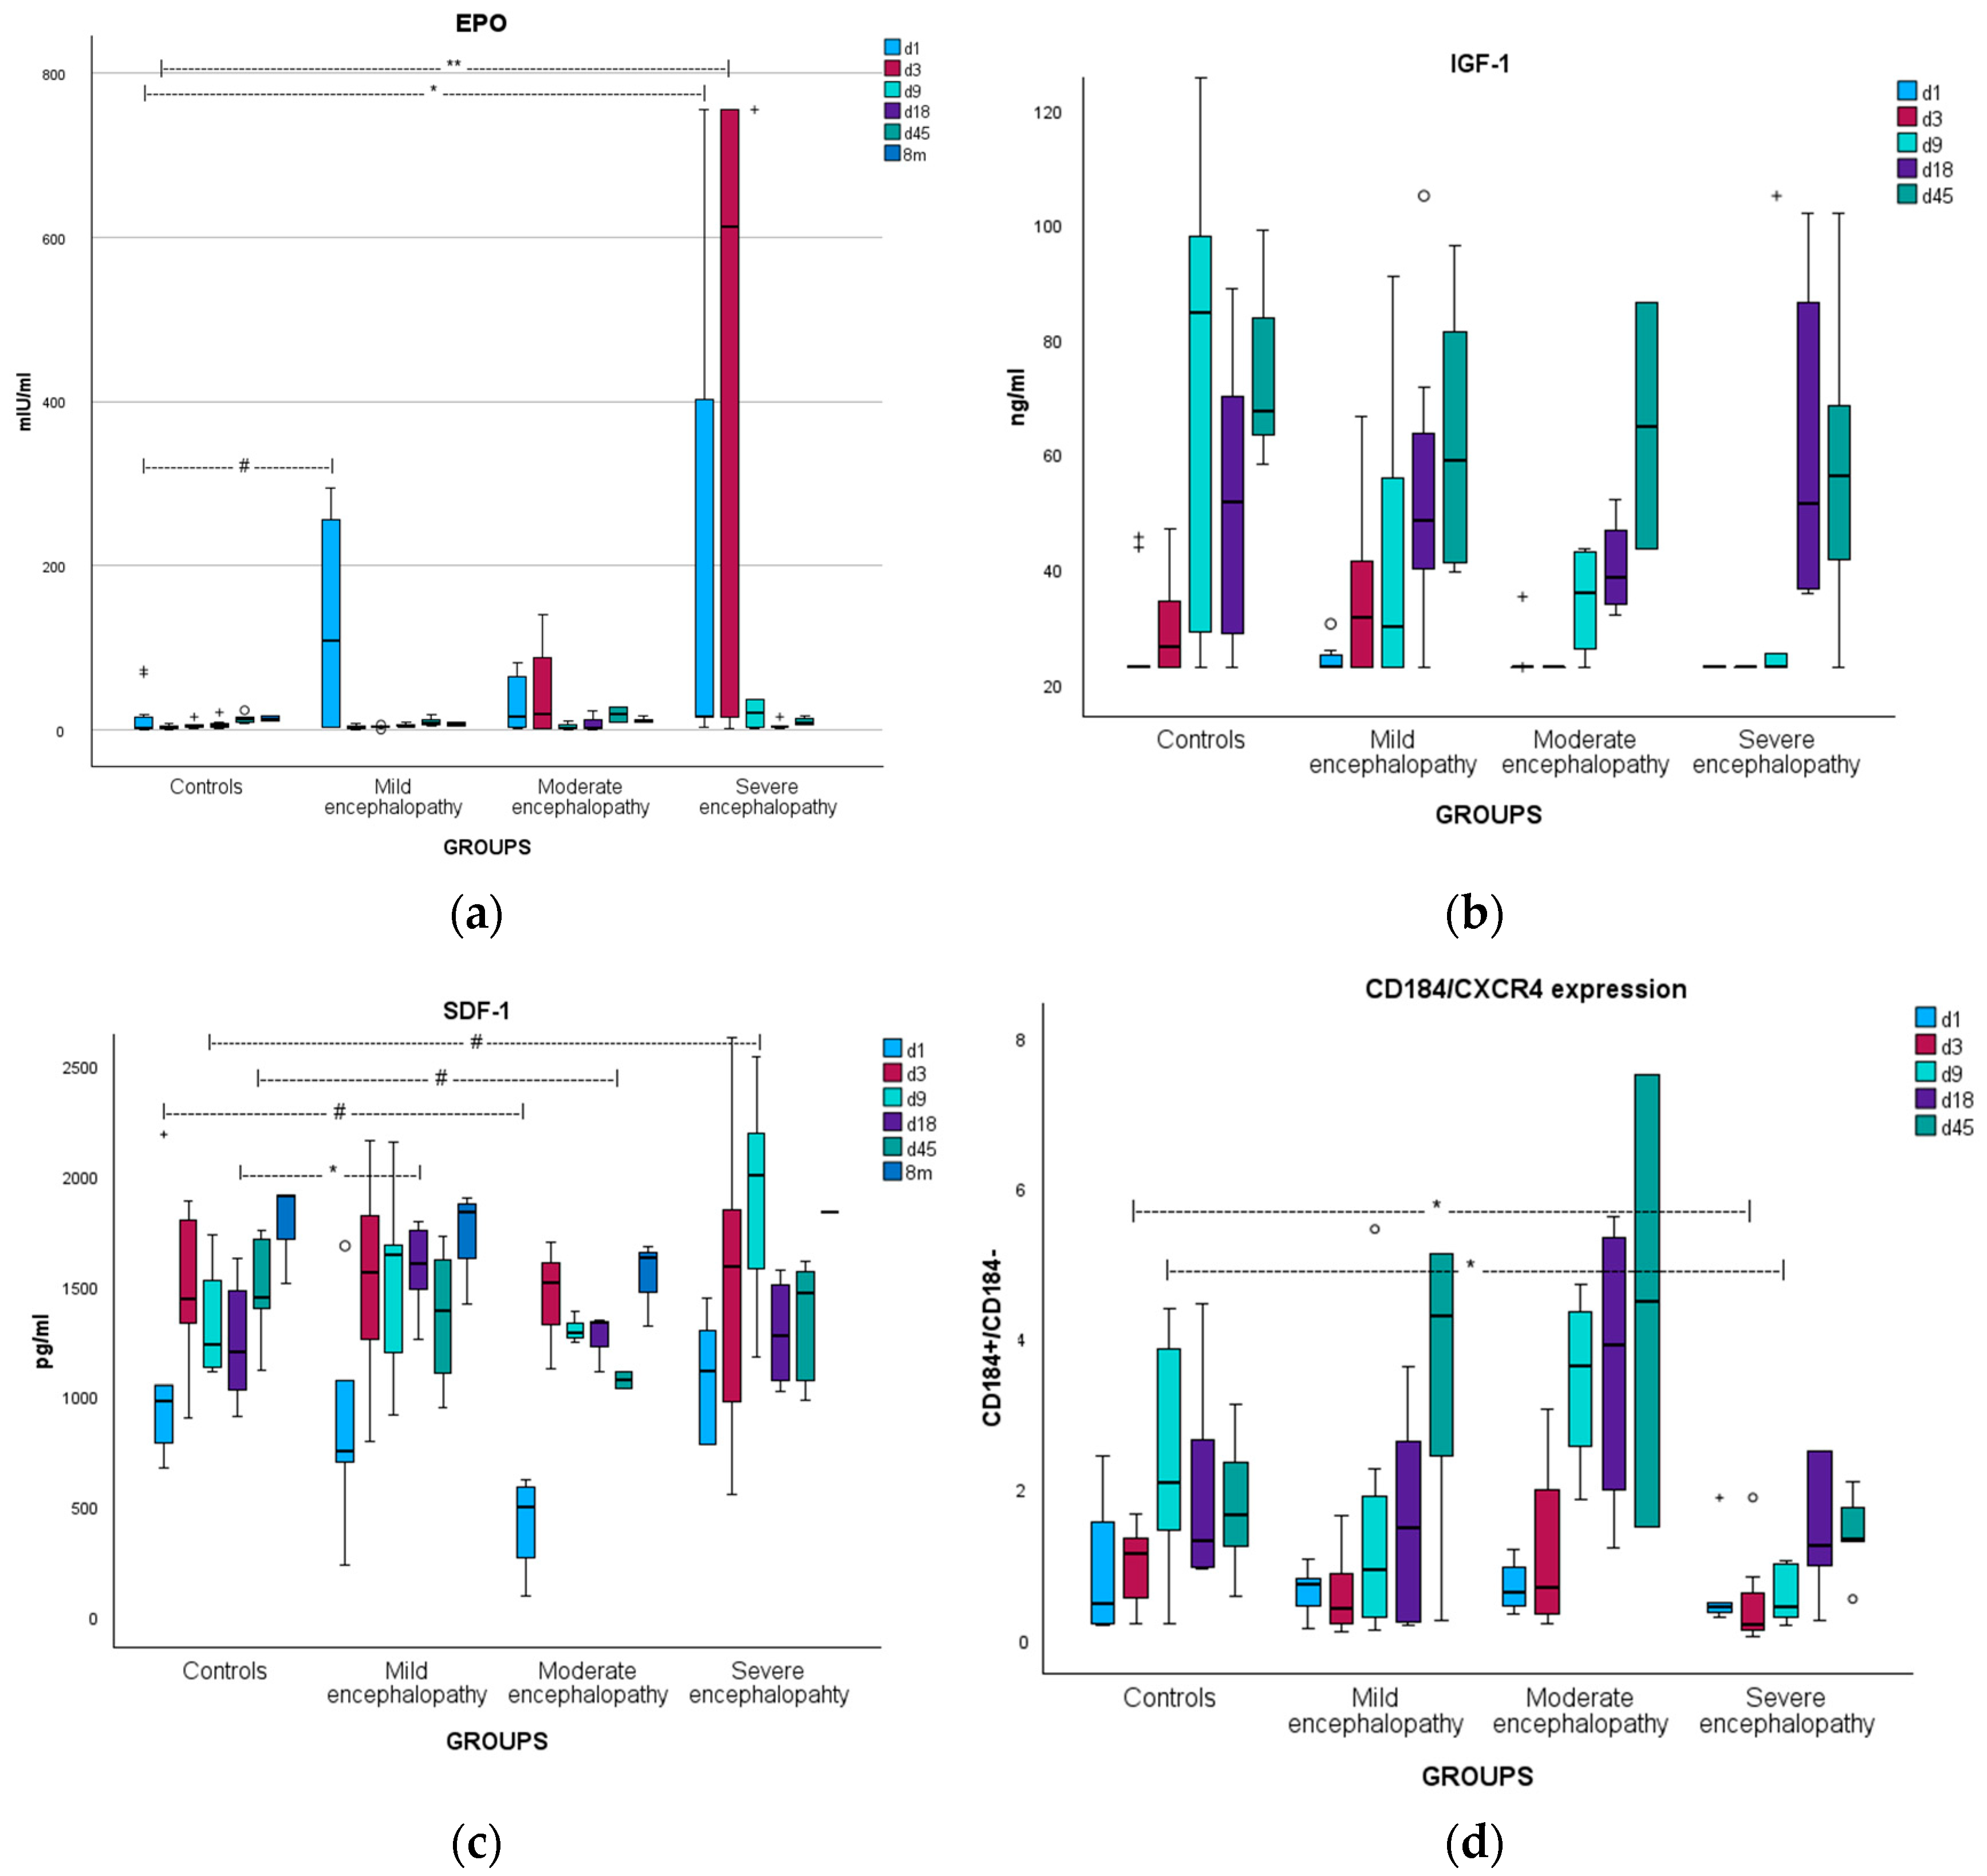

3.2. Erythropoietin

3.2.1. Kinetics

3.2.2. Correlations

3.3. Insulin-like Growth Factor-1

3.3.1. Kinetics

3.3.2. Correlations

3.4. Stromal Cell-Derived Factor-1

3.4.1. Kinetics

3.4.2. Correlations